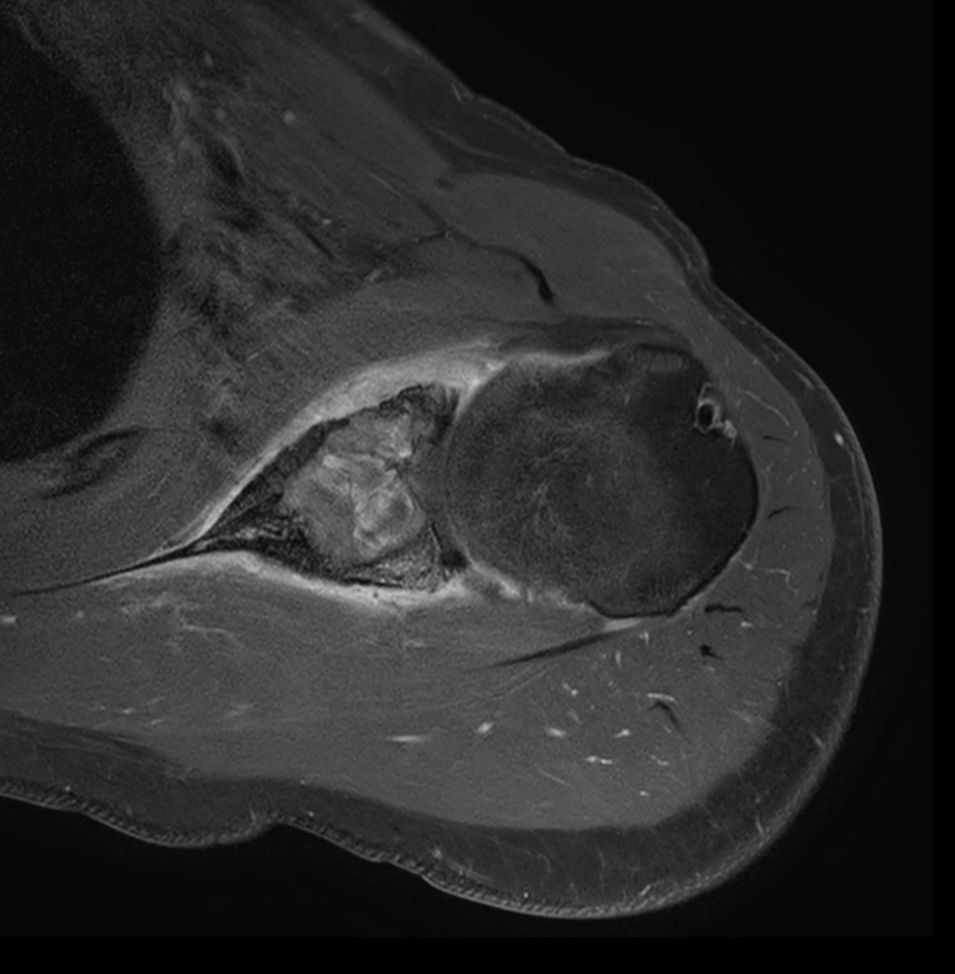

Patient with a shoulder tumor. Compressed SENSE acceleration is included to speed up sequences while maintaining equal image quality. mDIXON XD TSE in included (pre- and post-gadolinium injection) providing uniform, complete and consistent fat-free imaging. Besides the regular DWI EPI, a high resolution diffusion method is also included.

Coronal T1w mDIXON XD TSE - Compressed SENSE (Water only)

Coronal T1w mDIXON XD TSE - Compressed SENSE (In Phase)

Coronal T1w mDIXON XD TSE - Compressed SENSE (Water only) - Post-gado

Coronal T1w mDIXON XD TSE - Compressed SENSE (In Phase) - Post gado